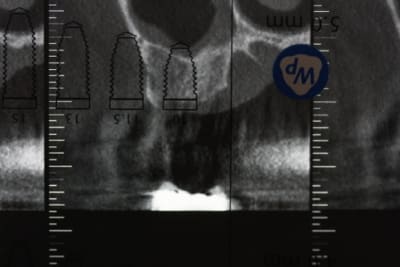

cas tout frais de cette après-midi

passage uniquement des ostéotomes pour cette 17 extraite il y a 3 mois 1/2

ostéotome à 6 mm:

1,5 à 2,2

2,2

2,8

3,5

bio-oss avec le 3,5

un coup de 4,2 sur 2 mm pour marquer l'entrée

mise en place d'un WP speedy: stabilité final de 30 N

mise en place de la vis de cica

1 point blair donati modifié et hop 40 mn

pour une extraction récente je trouve que l'alvéole s'est bien ossifiée, tu ne trouves pas ?

comment gères-tu la différence de niveau entre les versants palatins et vest ? tu t'es retrouvé en fin de chir avec une petite déhiscence palatine ?

une muqueuse aussi épaisse, c'est tout bon pour éviter une perf, j'aurais aimé avoir celle-la pour ma première chir

sur d'autres coupes on voit les anciennes alvéoles des racines vestibulaire, mais cette dent n'avait pas de racine palatine ( ancienne amputation ????)

et puis à 3 mois c'est souvent déjà pas mal ossifié, mais pas toujours très radio-opaque (200j pour reminéraliser)